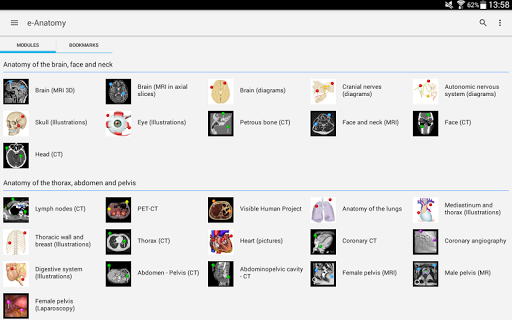

جديد: يمكنك الآن تصفية الوحدات حسب المنطقة أو نوع المحتوى حتى تتمكن من العثور على الوحدة التي تبحث عنها بشكل أسرع.

-يمكنك الآن فرز الوحدات حسب الطريقة

- وحدتان جديدتان: الدماغ - TOF والأوعية الدموية الدماغية ، أطلس التشريح الوعائي العصبي الطبيعي لشرايين الدماغ على الأوعية الدموية الدماغية. - تم إعادة صياغة الواجهة. - تتوفر علامة تبويب جديدة باسم "QuickLinks" ، ترسل وحدات في أقسام من جسم الإنسان وتسمح لك بالسفر السريع إلى الوحدات التي تبحث عنها. الخلل الصغيرة الثابتة.